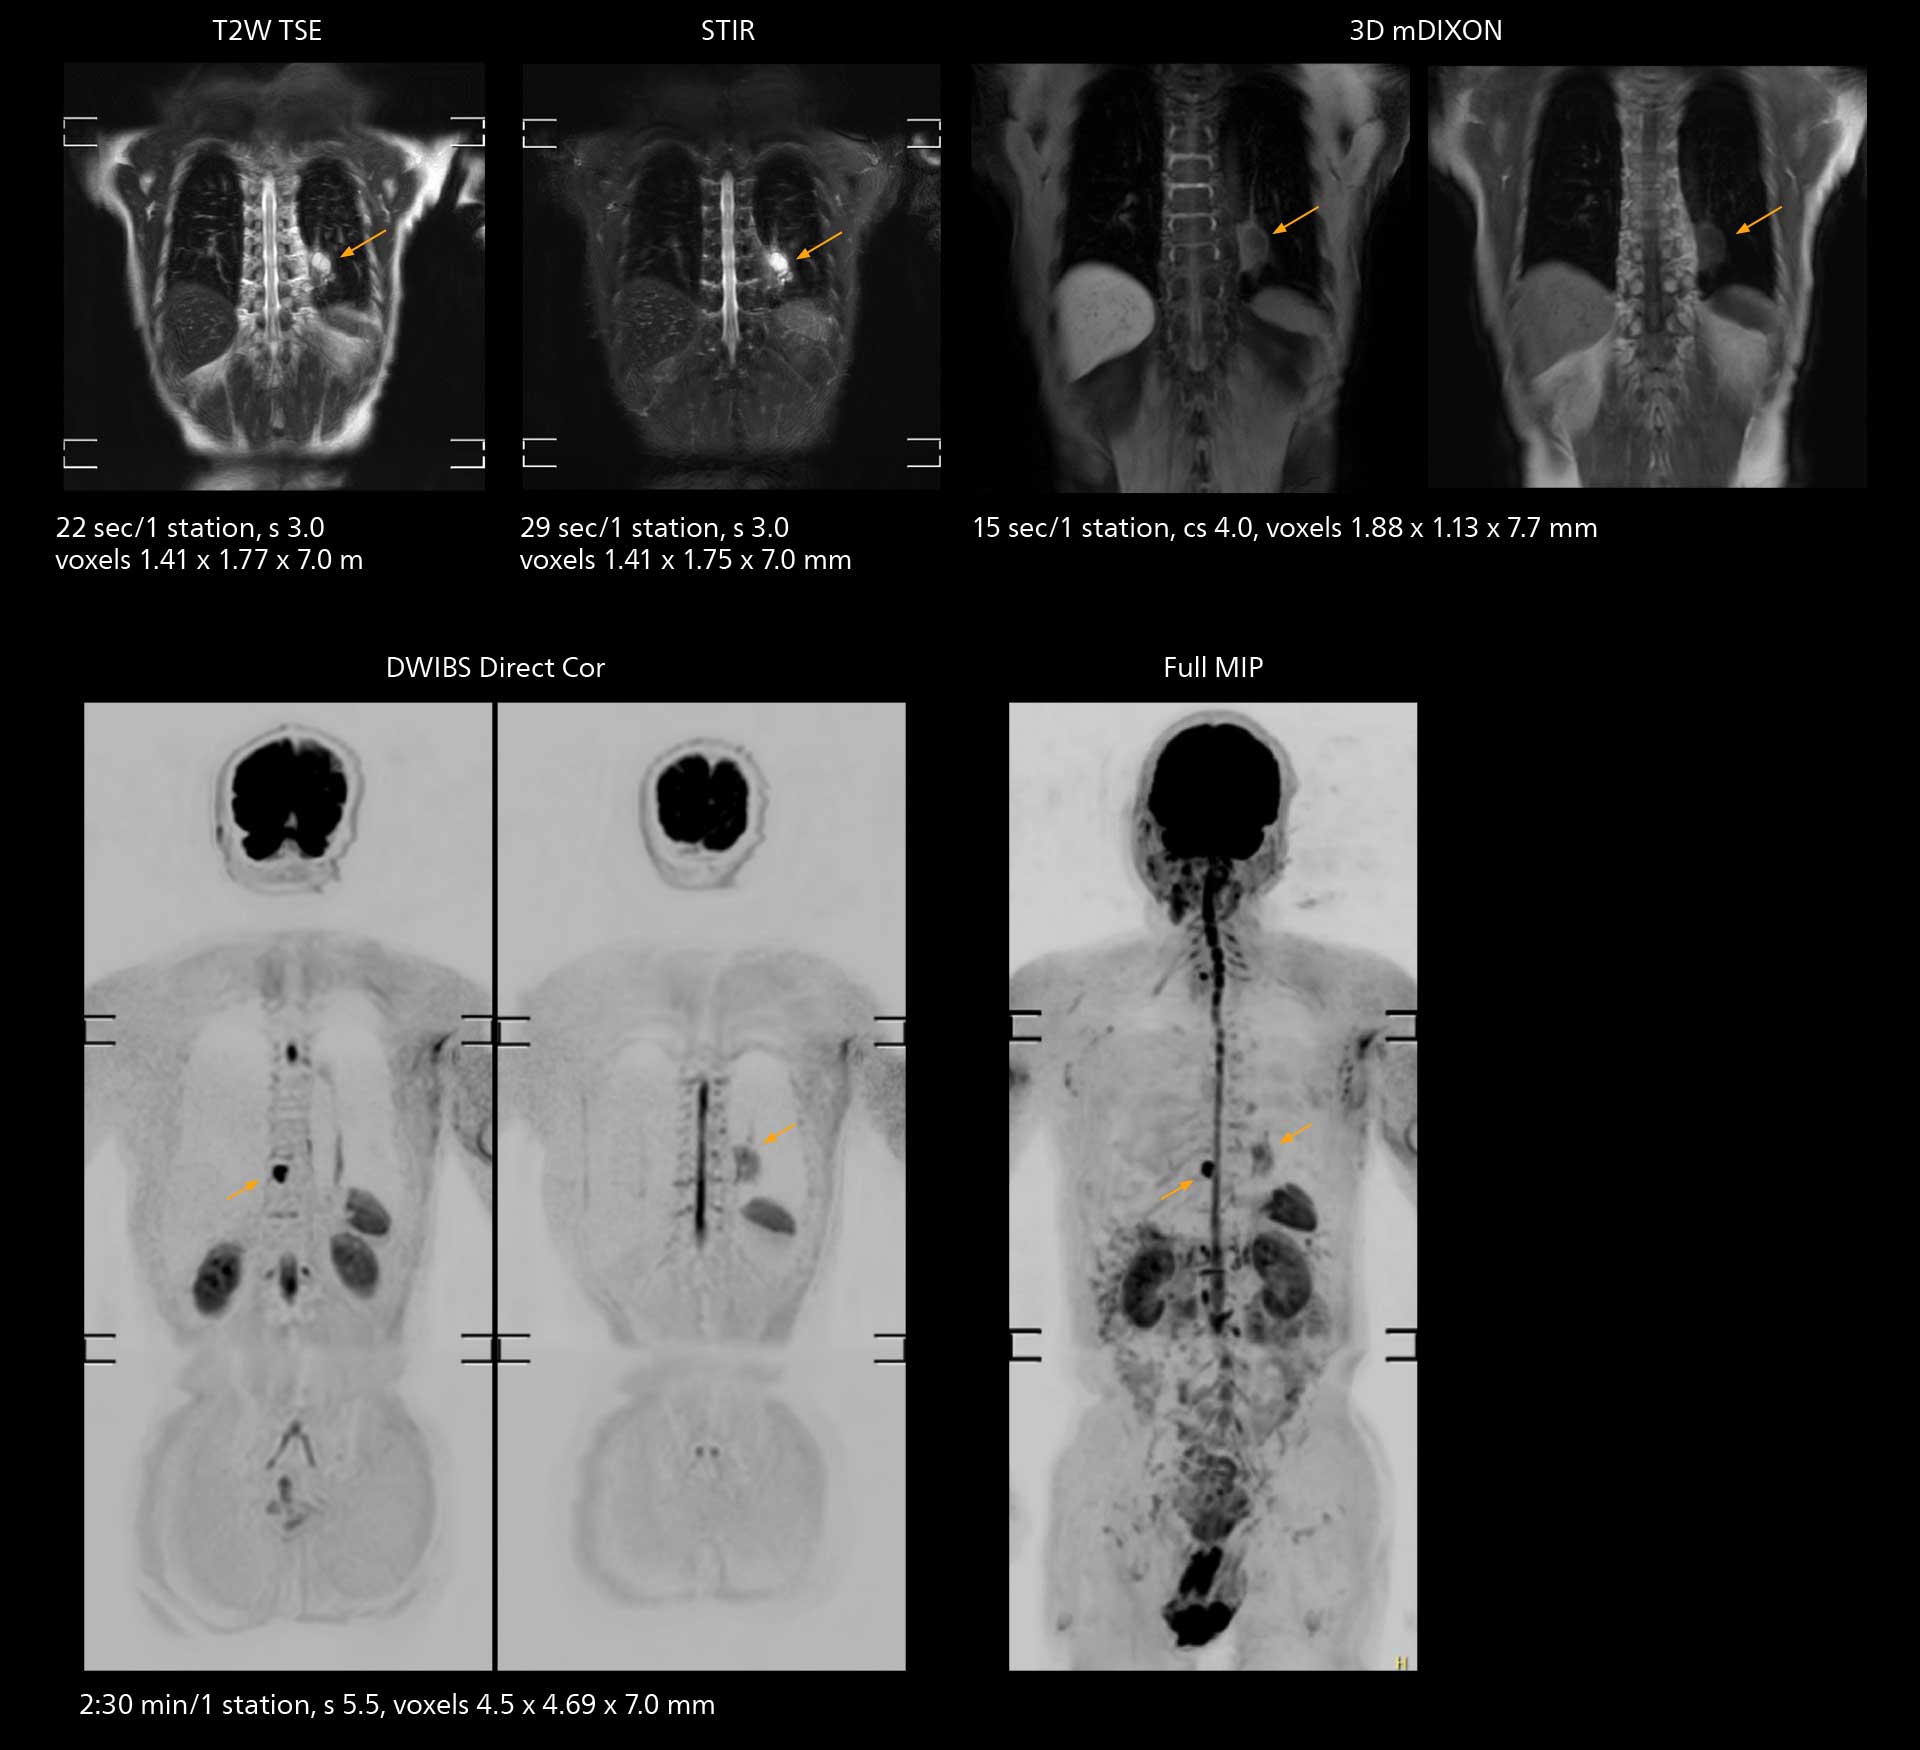

With SmartPath to Elition X, the MRCP examinations at Sannodai Hospital benefit from VitalEye: respiratory synchronization is possible without respiratory belt positioning and image quality is excellent.